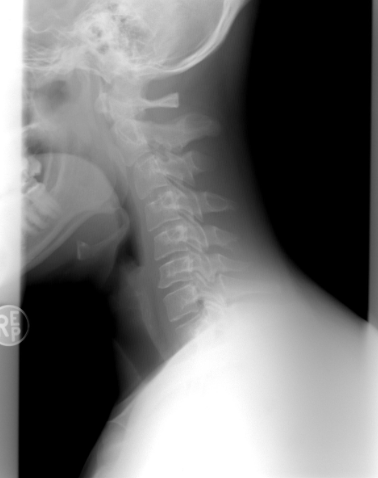

먼저 정상적인 목뼈(경추)는 C자 형태로 자연스럽게 굴곡을 이루고 있습니다. 이 곡선은 머리의 무게를 효율적으로 분산시키는 역할을 하며, 척추와 전신에 걸리는 부담을 최소화합니다. 하지만 거북목이 되면 경추의 C자 커브가 사라지고 일자로 변형되거나 심할 경우 역C자형으로 변하기도 합니다.

머리는 평균 약 4~5kg 정도 무게를 가집니다. 정상 자세에서는 이 무게가 척추를 따라 균등하게 분산되지만, 고개가 15도 앞으로 기울어질 때마다 목에 가해지는 하중은 약 12kg, 30도일 때는 18kg, 45도일 때는 무려 22kg까지 증가합니다. 거북목 상태가 심할수록 목과 어깨 주변 근육은 이 무거운 하중을 버티기 위해 끊임없이 긴장하게 됩니다.